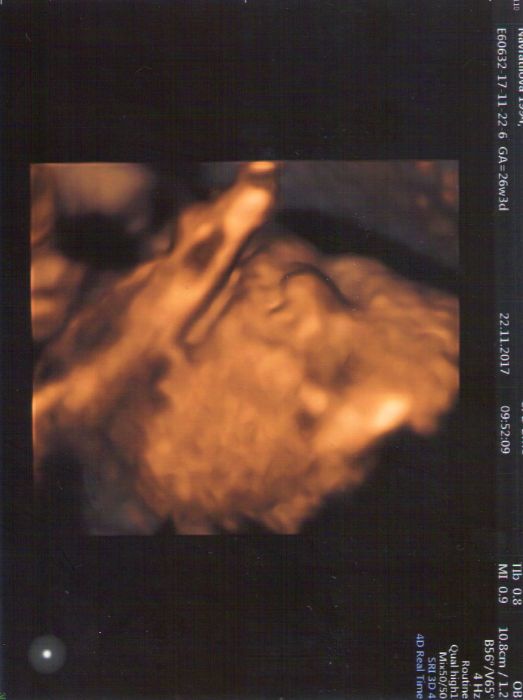

Mam spatny internet, tak snad se mi to odesle. V pondeli jsem byla na kontrole, srdicko v poradku, velikost odpovida stari tehotenstvi (ale miry netusim), deloha dva prsty nad pupek, cipek dobry. Dostala jsem zadanky na cukr, protilatky a krevni obraz. Uz se moc tesim. Mam si pohlidat, at cukr berou ze zily, ne z prstu, ze jsou zkreslene vysledky, proto se od toho upustilo. Dloubek obcas dloube, zatim je poloha uplne blba, tak snad se otoci hlavickou dolu. O placente mi nikdo nic nerikal. Na velky uzv jdu az nekdy v lednu. Bricho uz mam poradne. Mazu se olejickem, ale ve sprse jsem se vylekala, ze mi popraskaly prsa. Nastestito asi byly jenom prosvitajici cevy. Vecer a v noci trpim s tim strilenim, vubec se to nelepsi. Ale porad doufam...